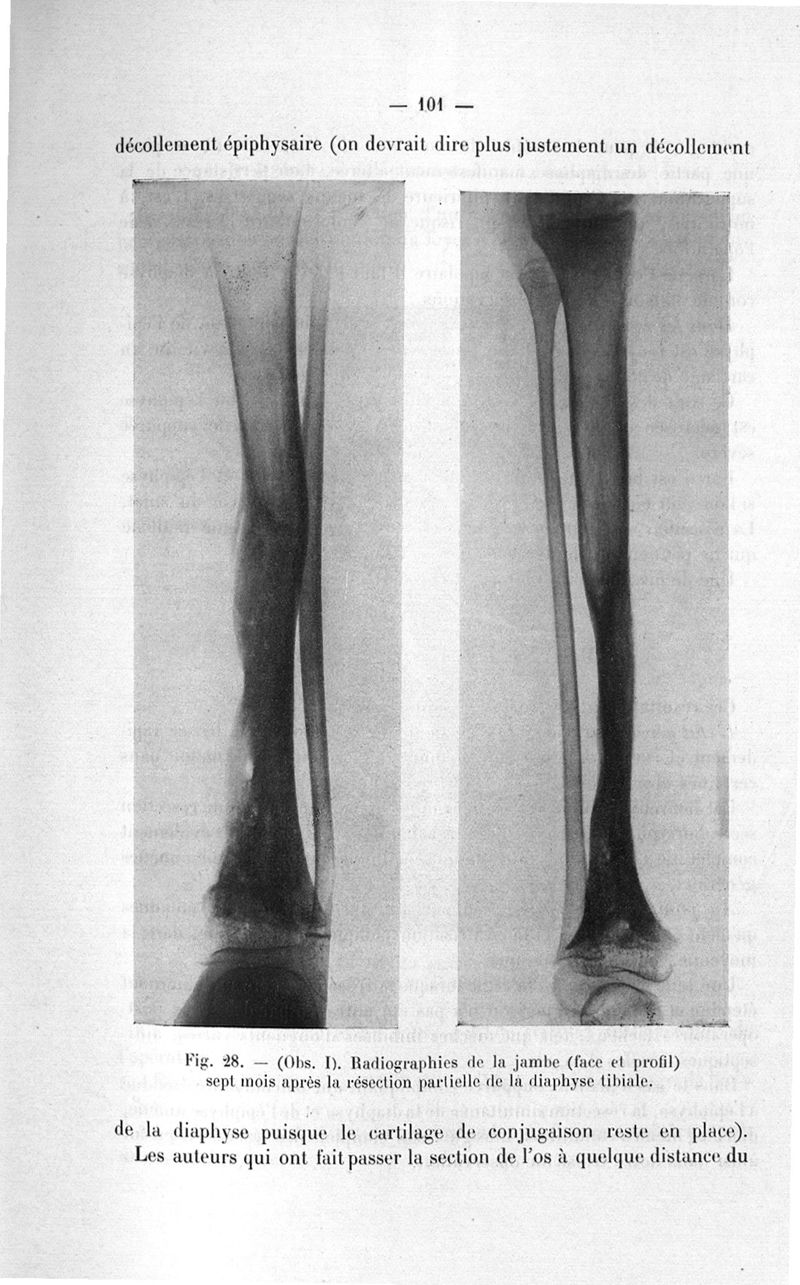

Leveuf, Jacques.

Exposé des titres et travaux scientifiques

Paris, Masson et Cie, 1926.